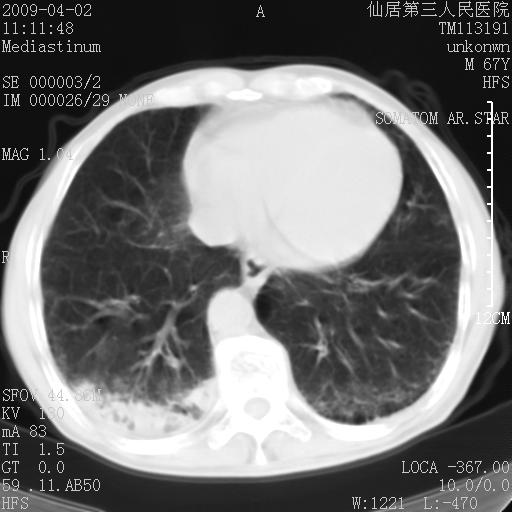

患者老年男性,乏力畏寒来诊,摄胸片示右下肺感染性病变,抗炎两周后复查胸片,无好转有进展。

后做ct平扫表现如下:

考虑右肺炎症可能性大,不除外细支气管肺泡癌

是否还要考虑肺间质纤维化,建议hrct扫描。

病灶呈蜂窝征,纵隔多个淋巴结肿大;肺泡癌需考虑

我认为普通的感染应该可以除外,间质性肺炎可能性较大,但如何解释纵膈的淋巴结肿大呢